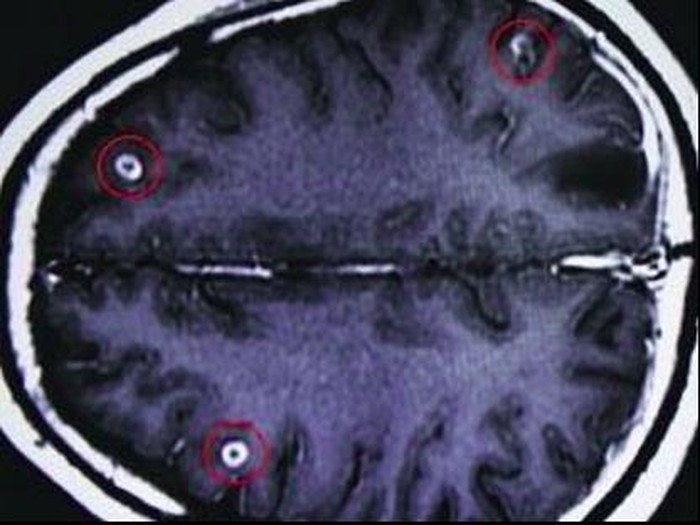

5. Pasien pria asal Guangzhou

|

Foto: Canadian Family Physician

Dokter di Guangzhou No. 8 People's Hospital yang menangani pria tersebut yakin jika cacing pita dalam jumlah banyak itu berasal dari daging atau ikan mentah yang terkontaminasi. Beberapa jenis obat pun diberikan untuk memusnahkan cacing-cacing pita tersebut.

"Mengonsumsi makanan yang tidak dimasak dan terkontaminasi telur cacing pita bisa menyebabkan cysticercosis, jika cacing dewasa yang menetas dari telur memasuki aliran darah," kata sang dokter. Selain itu, perlu diwaspadai bahwa meski sudah diasinkan atau diasap, kemungkinan kontaminasi larva masih tetap ada.

Cara penyajian juga patut diperhatikan karena piring yang kurang bersih pun bisa membuat ikan mentah terkontaminasi.